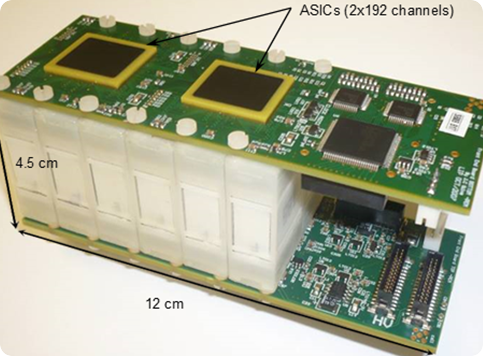

Our Avalanche Photodiode (APD) based technology for PET was developed by a R&D Consortium including PETsys S.A., with a focus on research and development. The R&D Consortium licensed this technology to PETsys SA. The APD-based photon detectors use matrices of LYSO scintillation crystals coupled to APD arrays. The APD signals are readout and sampled by a dedicated ASIC with 192 channels.

Several crystal-APD units and the corresponding frontend electronics are assembled in detector modules. Our APD-based detector module has 384 LYSO 2x2x20 mm crystals and covers a detection area of ~4x8 cm. One of the advantages the APDs is the capability of performing the double readout of the scintillation crystals, which allows to calculate the DoI of the detected photons. Associated to the fine detector pitch (2x2 mm) and the one-to-one coupling between crystal and APD pixels, the DoI capability permits an excellent spatial resolution of the order of 1.3 mm over the whole Filed-of-View.

These systems comprise 12288 APD's and 6144 scintillation crystals, organized into two opposing detector plates. One of these is located at ICNAS in Coimbra (PT) - (Fig. 5).